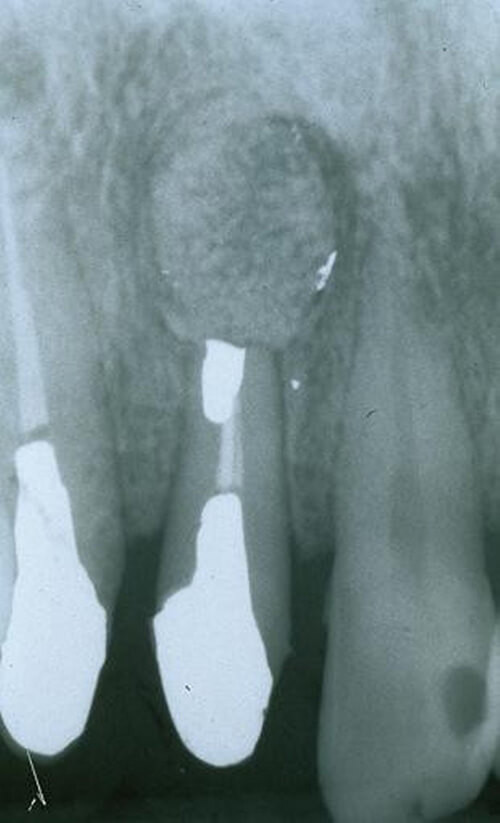

<歯根端切除術+嚢胞摘出術>

嚢胞と原因の歯の根の一部を一緒に摘出します。

※術後のレントゲンで嚢胞を摘出した部位に骨の形成を認めます。